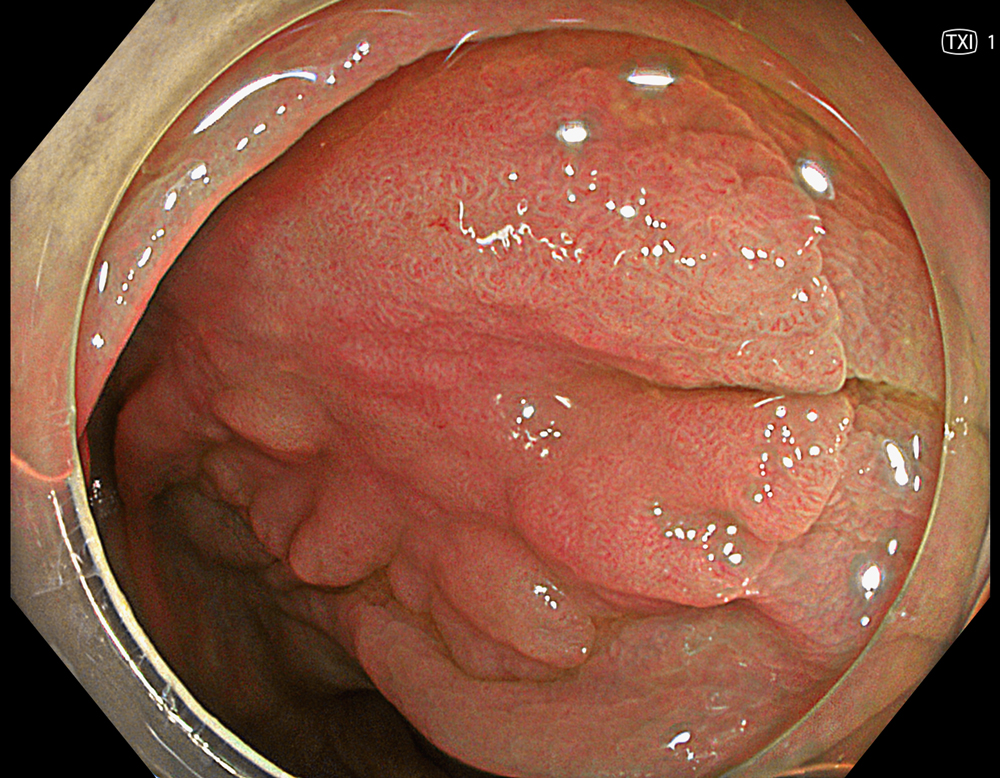

3. LST-NG with TXI (Mode 2)

TXI mode 2 enhances texture and brightness while preserving natural color tone, allowing clearer delineation of the lesion margin and overall extent.